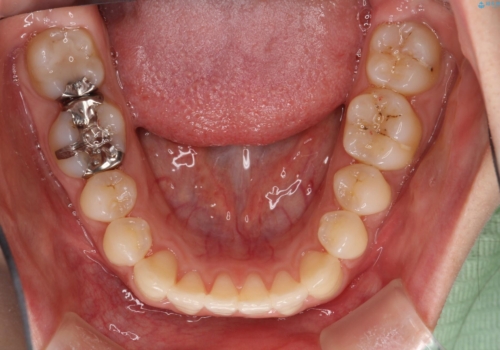

抜歯なし/インビザラインによるマウスピース矯正にて治療を行いました。

内側に入り込んでしまっている歯を出してくることに非常に時間がかかりましたが、一度歯を歯茎の方へ押し込みそして前へ出してくる2段階の治療を行いました。